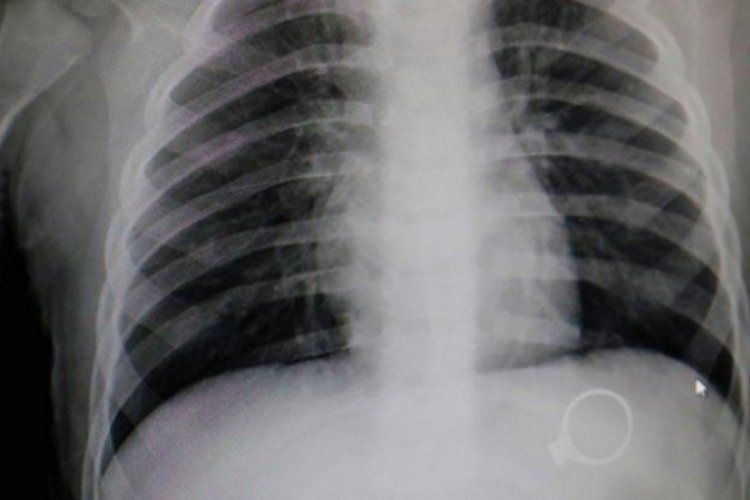

Göğüs Röntgeni Neden Göğüs Röntgeni Çektirmeliyim